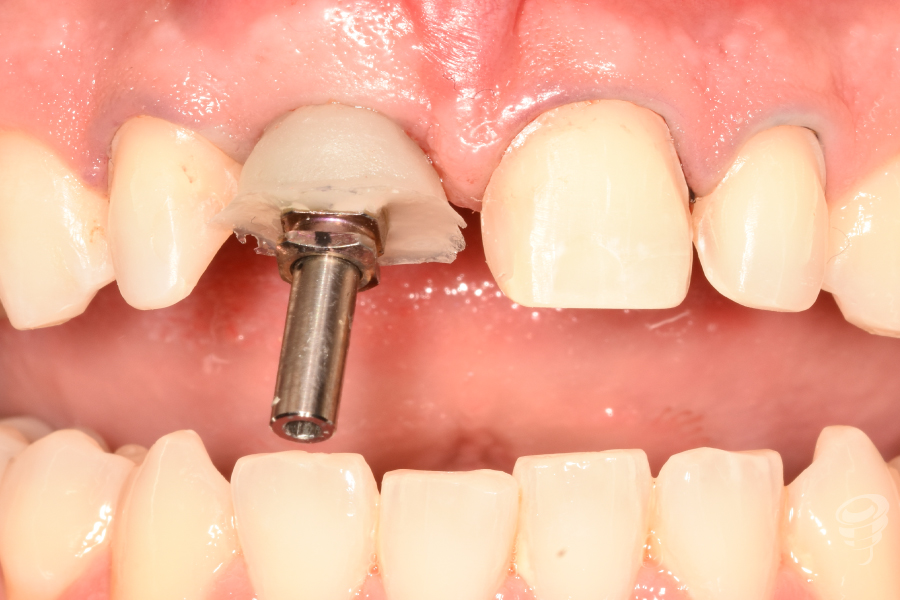

- Provisionalización: Pilar titanio personalizado + corona provisional de resina acrílica (sin contacto oclusal), con la colocación de puntos suspensores para estabilizar la encía y márgenes gingivales.

Figura 22

Figura 23

Figura 24

Figura 25